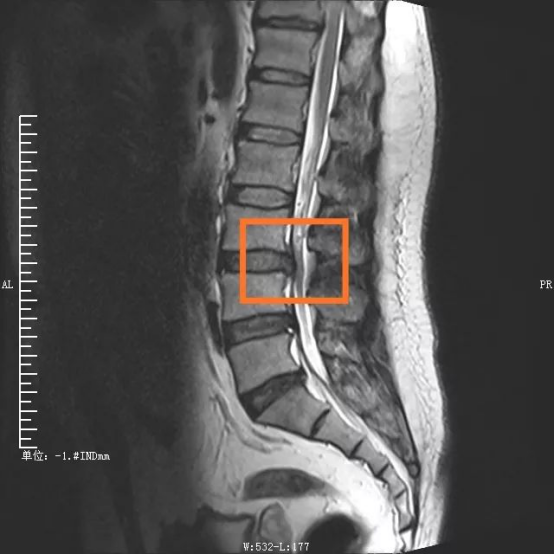

手術が決まるまで D総合病院整形外科を受診。 レントゲン(腰部いろいろな角度で)とMRI画像から「腰椎分離すべり症」と診断される。 また小児期の激しい運動による分離ではなく、先天的に弱い部分が分離したのではと指摘された(先天的内視鏡(ped)を用いた手術 腰椎椎間板ヘルニア、腰部脊柱管狭窄症、頚椎神経根症などで適応のある患者さんに対して内視鏡を用いた手術を行っています。 慶友脊椎内視鏡センター 代表的な脊椎手術を受ける患者さんの入院中の経過変性すべり症の患者さんのfess (pel/fel) 治療です。 才男性 第4/5腰椎変性すべり症をともなう脊柱管狭窄症のpel治療です。 手術前 レントゲン 第4/5腰椎のすべり症です。 手術前mri 大きい神経(ばび神経)の通り道が途切れています(中央図)。